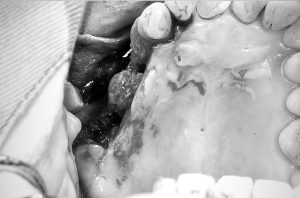

①術前

歯肉を切開、剥離前の写真

歯肉の上から見てもデコボコしている。